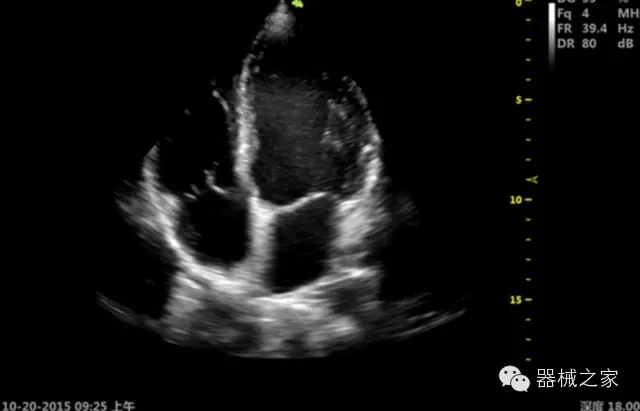

經(jīng)典產(chǎn)品:S8EXP

臨床圖片賞析

產(chǎn)品特點(diǎn)

優(yōu)異的成像技術(shù)

·亞陣元技術(shù):獨(dú)有的亞陣元技術(shù),對獨(dú)立晶片做二次切割,減少旁瓣偽像,增加臨床診斷的準(zhǔn)確性;

·μ-Scan微米成像技術(shù):開立獨(dú)有的μ-Scan技術(shù),還原出真實(shí)細(xì)膩、層次對比優(yōu)異的二維圖像;

·倒相諧波成像技術(shù):倒相諧波技術(shù)在去除基波信號(hào)的基礎(chǔ)上獲取兩倍二次諧波信號(hào),提高組織圖像的對比分辨力;

·智能微血流成像技術(shù):智能微血流捕捉技術(shù)可以提取出隱藏在背景噪聲中的弱血流信號(hào),大大提高低速血流的敏感性;

·心功能綜合指數(shù)(TEI指數(shù)):用于左、右心室整體心臟收縮舒張功能評估的測量方法;

·全方位可調(diào)M型:有利于更好的觀察心腔大小及室壁階段性運(yùn)動(dòng)的異常情況;

·組織多普勒成像(TDI):TDI可定量評價(jià)心肌運(yùn)動(dòng),判斷是否有局部病變,還可評價(jià)早期的舒張功能;